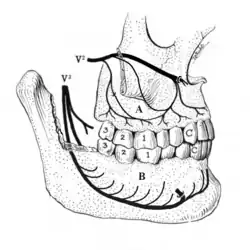

Disorders of the maxillary sinus can be referred to the upper back teeth. The posterior, middle and anterior superior alveolar nerves are all closely associated with the lining of the sinus. The bone between the floor of the maxillary sinus and the roots of the upper back teeth is very thin, and frequently the apices of these teeth disrupt the contour of the sinus floor. Consequently, acute or chronic maxillary sinusitis can be perceived as maxillary toothache,[36] and neoplasms of the sinus (such as adenoid cystic carcinoma)[37]: 390 can cause similarly perceived toothache if malignant invasion of the superior alveolar nerves occurs.[38]: 72 Classically, sinusitis pain increases upon Valsalva maneuvers or tilting the head forward.[39]